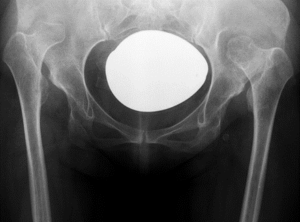

Для хирургического лечения диспластического коксартроза IV типа по Crowe разработан усовершенствованный деротационный имплантат, предназначенный для фиксации зоны подвертельной остеотомии. Биомеханические расчёты подтвердили прочностную надёжность конструкции, а первые операции продемонстрировали её высокую эффективность в стабилизации костных фрагментов при сложной анатомии. На данный момент ведётся клиническая апробация.

Строение стабилизирующей пластины для остеосинтеза зоны остеотомии при диспластических коксартрозах IV типа по Crowe